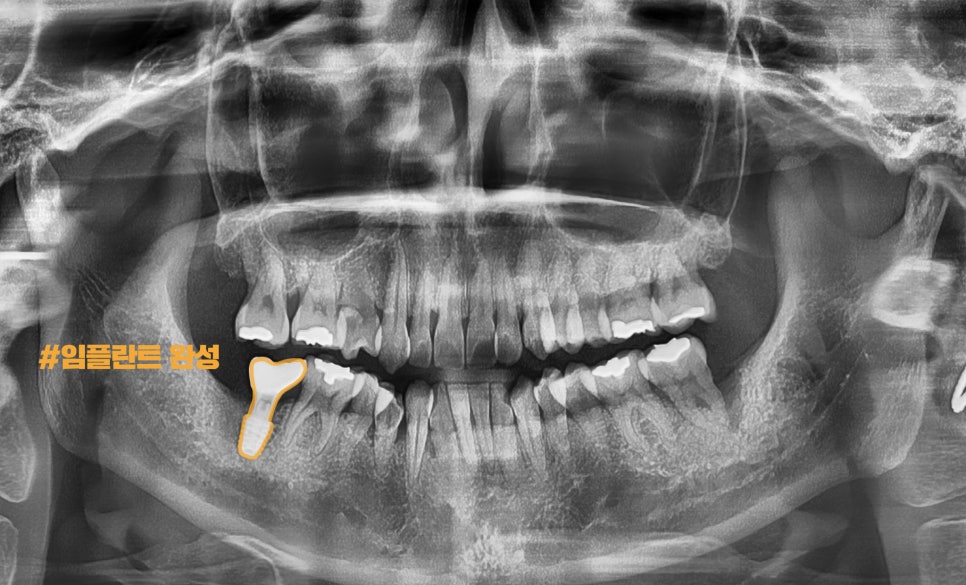

이후,

뼈세포와 Fixture가 만나서

서로 결합하는 기간을 갖게 되었으며

SCRP TYPE으로

지르코니아 크라운을 올려드렸습니다.